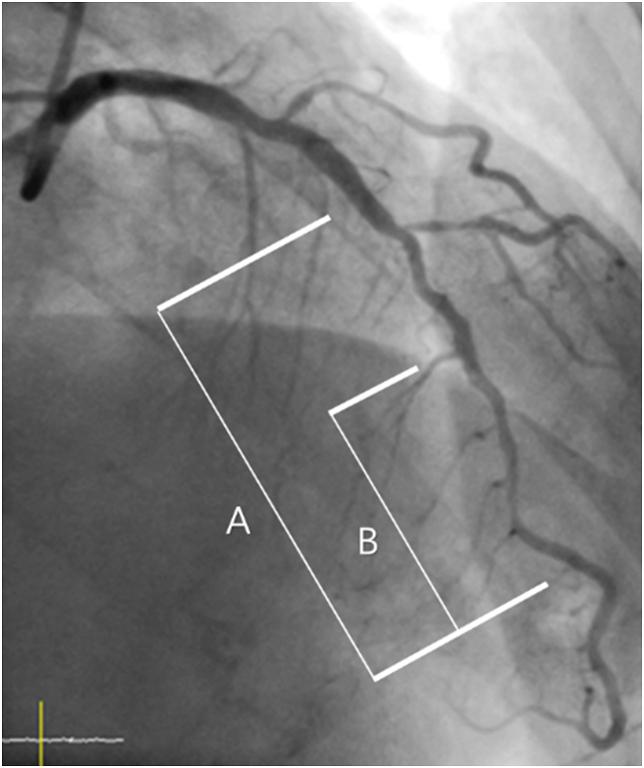

: Long-stenting, even with a second-generation drug-eluting stent (DES), is an independent predictor of restenosis and stent thrombosis in patients with long coronary lesions. Spot-stenting, i.e., selective stenting of only the most severe stenotic segments of a long lesion, may be an alternative to a DES. The purpose of this study is to compare the one-year clinical outcomes of patients with spot versus entire stenting in long coronary lesions using a second-generation DES.

This study is a randomized, prospective, multi-center trial comparing long-term clinical outcomes of angiography-guided spot versus entire stenting in patients with long coronary lesions (≥25 mm in length). The primary endpoint is target vessel failure (TVF) at 12 months, a composite of cardiac death, target vessel-related myocardial infarction, and target vessel revascularization (TVR). A total of 470 patients are enrolled for this study according to sample size calculations. This study will be conducted to evaluate the non-inferiority of spot stenting compared to entire stenting with zotarolimus-eluting stents (ZES).

长病变支架置入术,即使使用第二代药物洗脱支架(DES),仍是长冠状动脉病变患者再狭窄和支架血栓形成的独立预测因素。局部支架置入术,即仅对长病变中最严重狭窄段进行选择性支架置入,可能是DES的一种替代方法。本研究的目的是比较使用第二代DES对长冠状动脉病变患者进行局部与全程支架置入的一年临床结局。

本研究是一项随机、前瞻性、多中心试验,比较在长冠状动脉病变(长度≥25mm)患者中,血管造影引导下局部与全程支架置入的长期临床结局。主要终点是12个月时的靶血管失败(TVF),它是心源性死亡、靶血管相关心肌梗死和靶血管血运重建(TVR)的复合终点。根据样本量计算,共有470例患者纳入本研究。本研究将评估与佐他莫司洗脱支架(ZES)全程支架置入相比,局部支架置入的非劣效性。